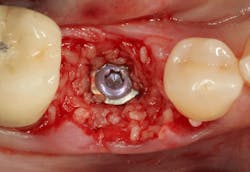

An osteotomy was then created, extending to the apical portion of the split ridge in preparation for implant placement. A bone-level tapered 4.1- x 12-mm implant was placed with a flat cover screw. A mixture of cancellous and cortical allograft particulate was infused with autogenous PRGF and packed around the implant on the mesial and distal aspects. The newly out-fractured buccal plate was positioned intimately adjacent to the buccal portion of the implant, and additional graft material was placed over the buccal plate to further augment the bone horizontally and reduce the risk of buccal-plate resorption during healing. A 25- x 30-mm Ossix Plus membrane was soaked in saline for three minutes and trimmed to extend 3–4 mm beyond the confines of the bone graft and roughly 1 mm from the adjacent teeth.

After the photo was taken to demonstrate the membrane placement, a periosteal elevator was used to further push the membrane under the lingual flap so that it draped intimately over the graft. The partial-thickness flap preparation made during initial incisions allowed for coronal positioning for tension-free primary closure. A CV-5 horizontal mattress suture was used to bring the buccal and lingual flaps together, and closure was completed with interrupted sutures.